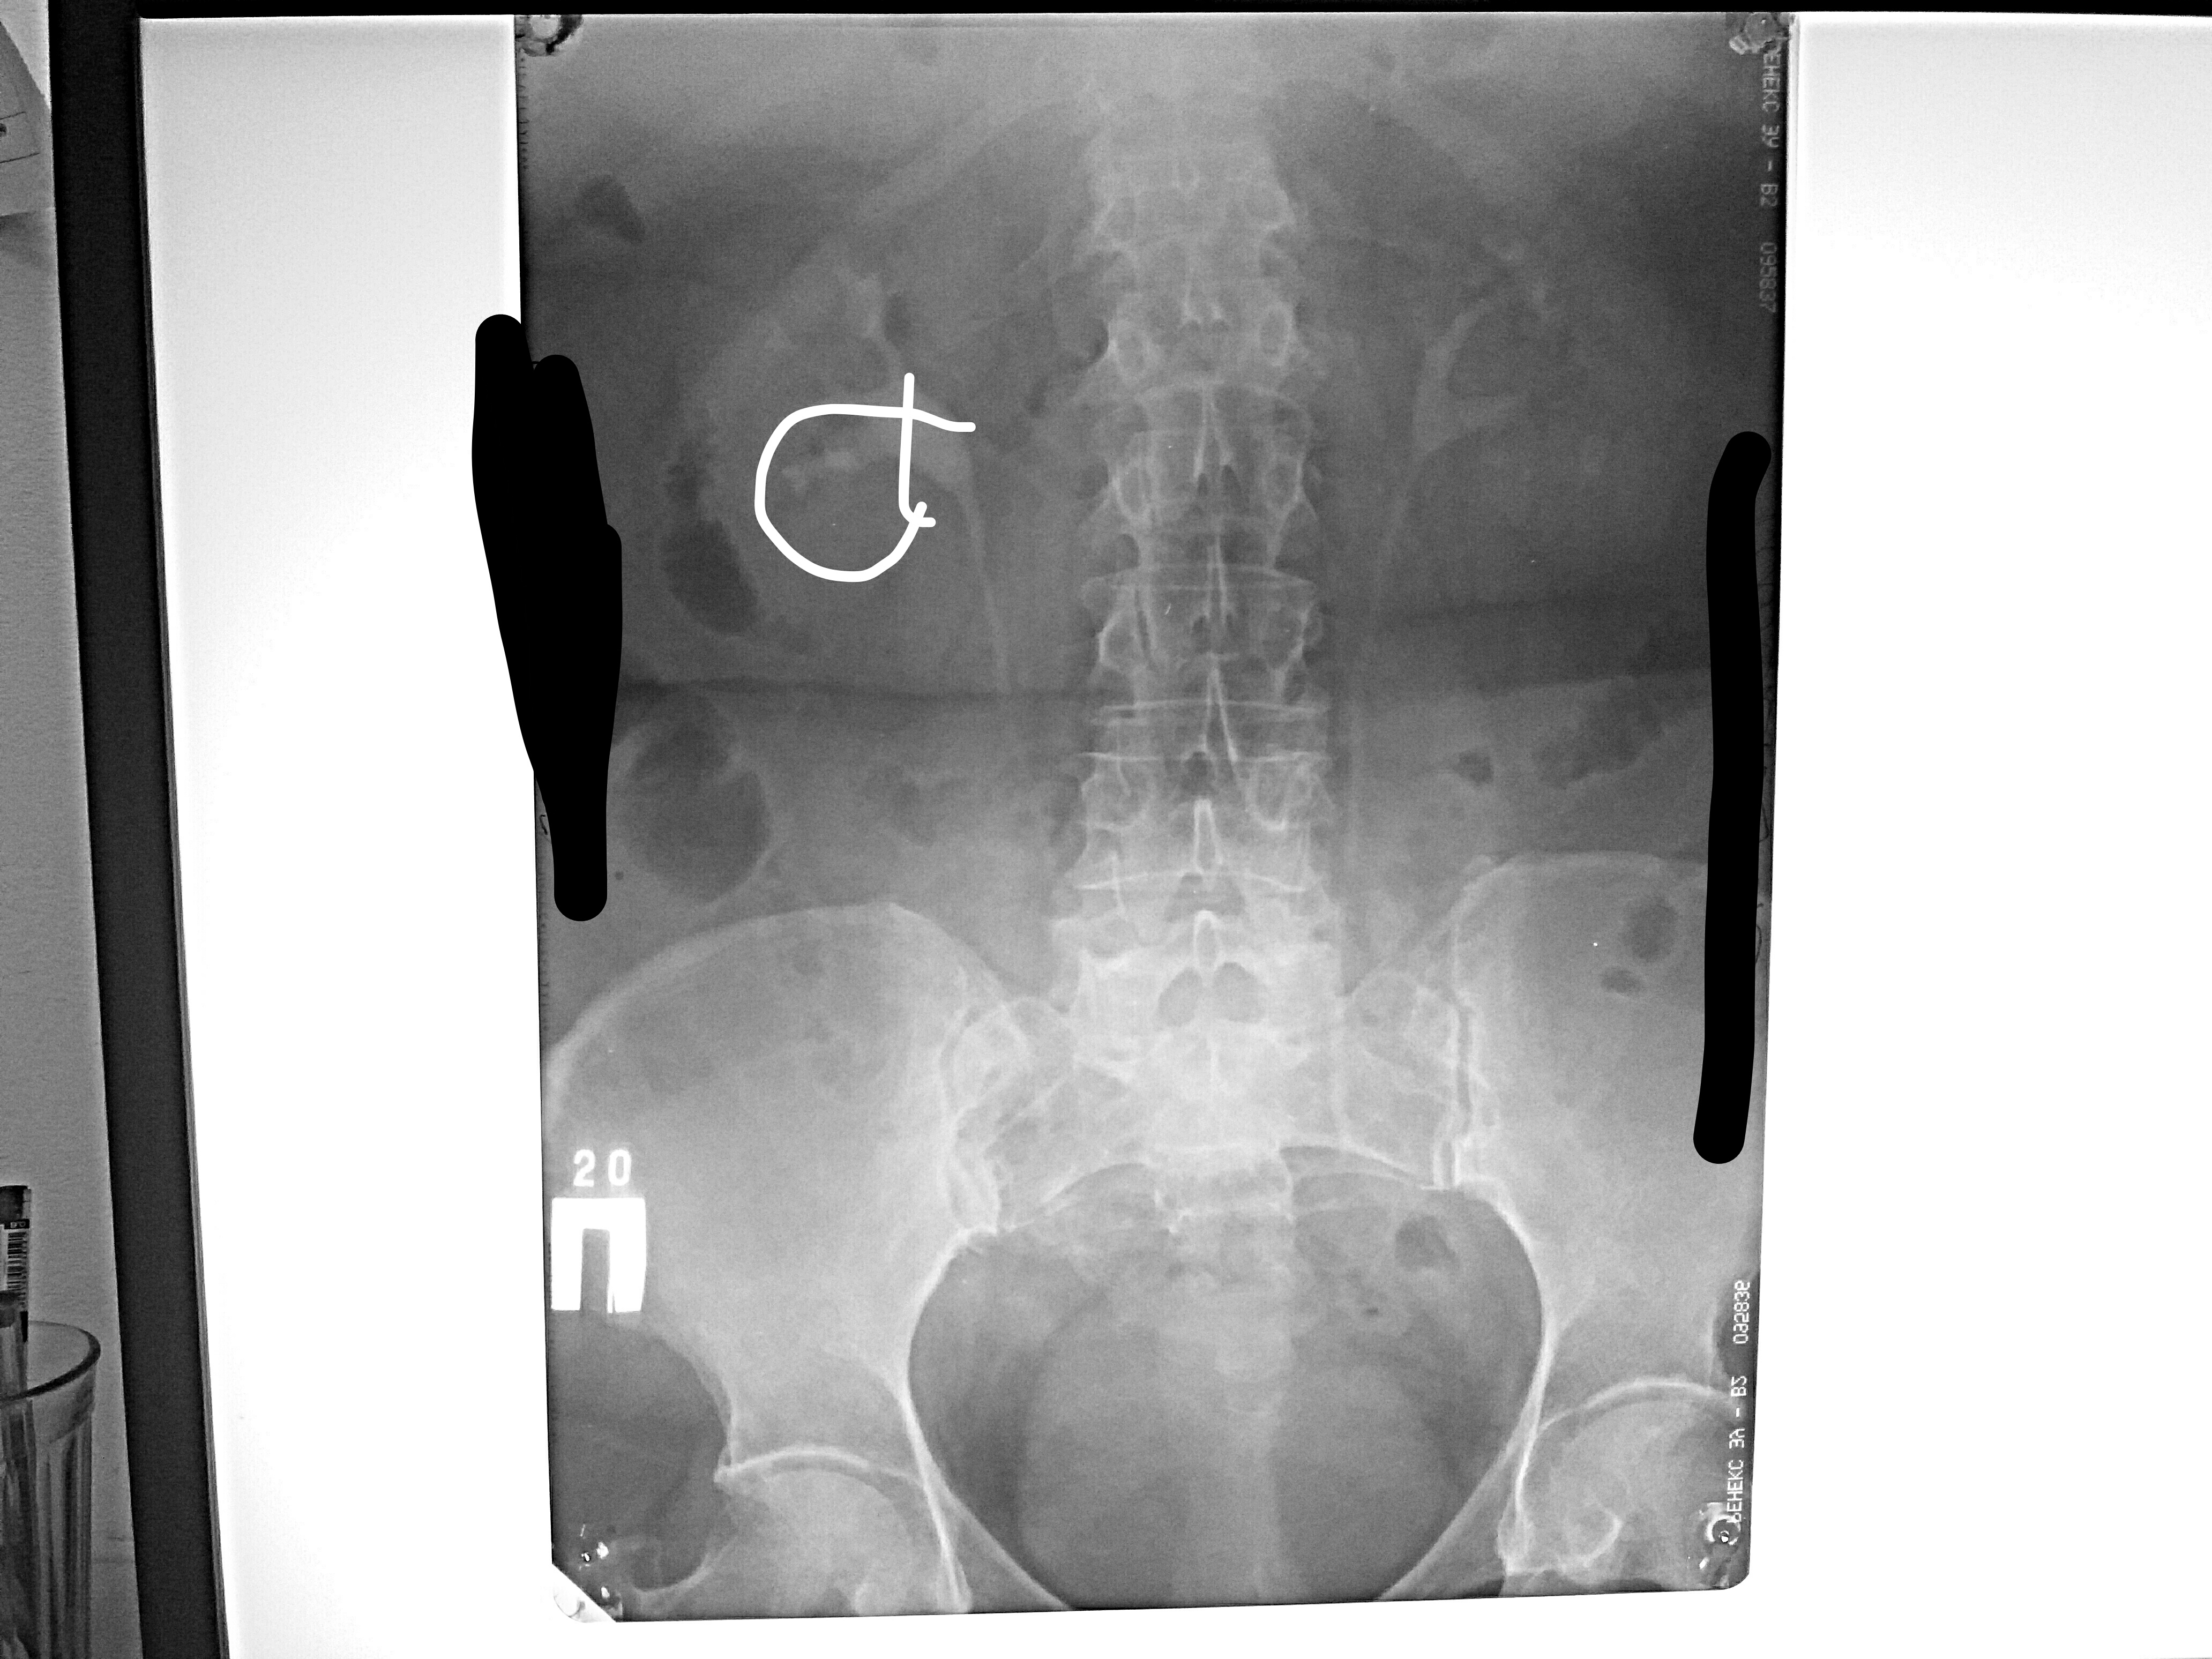

Медицинские изображения: Обзорная рентгенография урография

Раздел: Фокус на знании